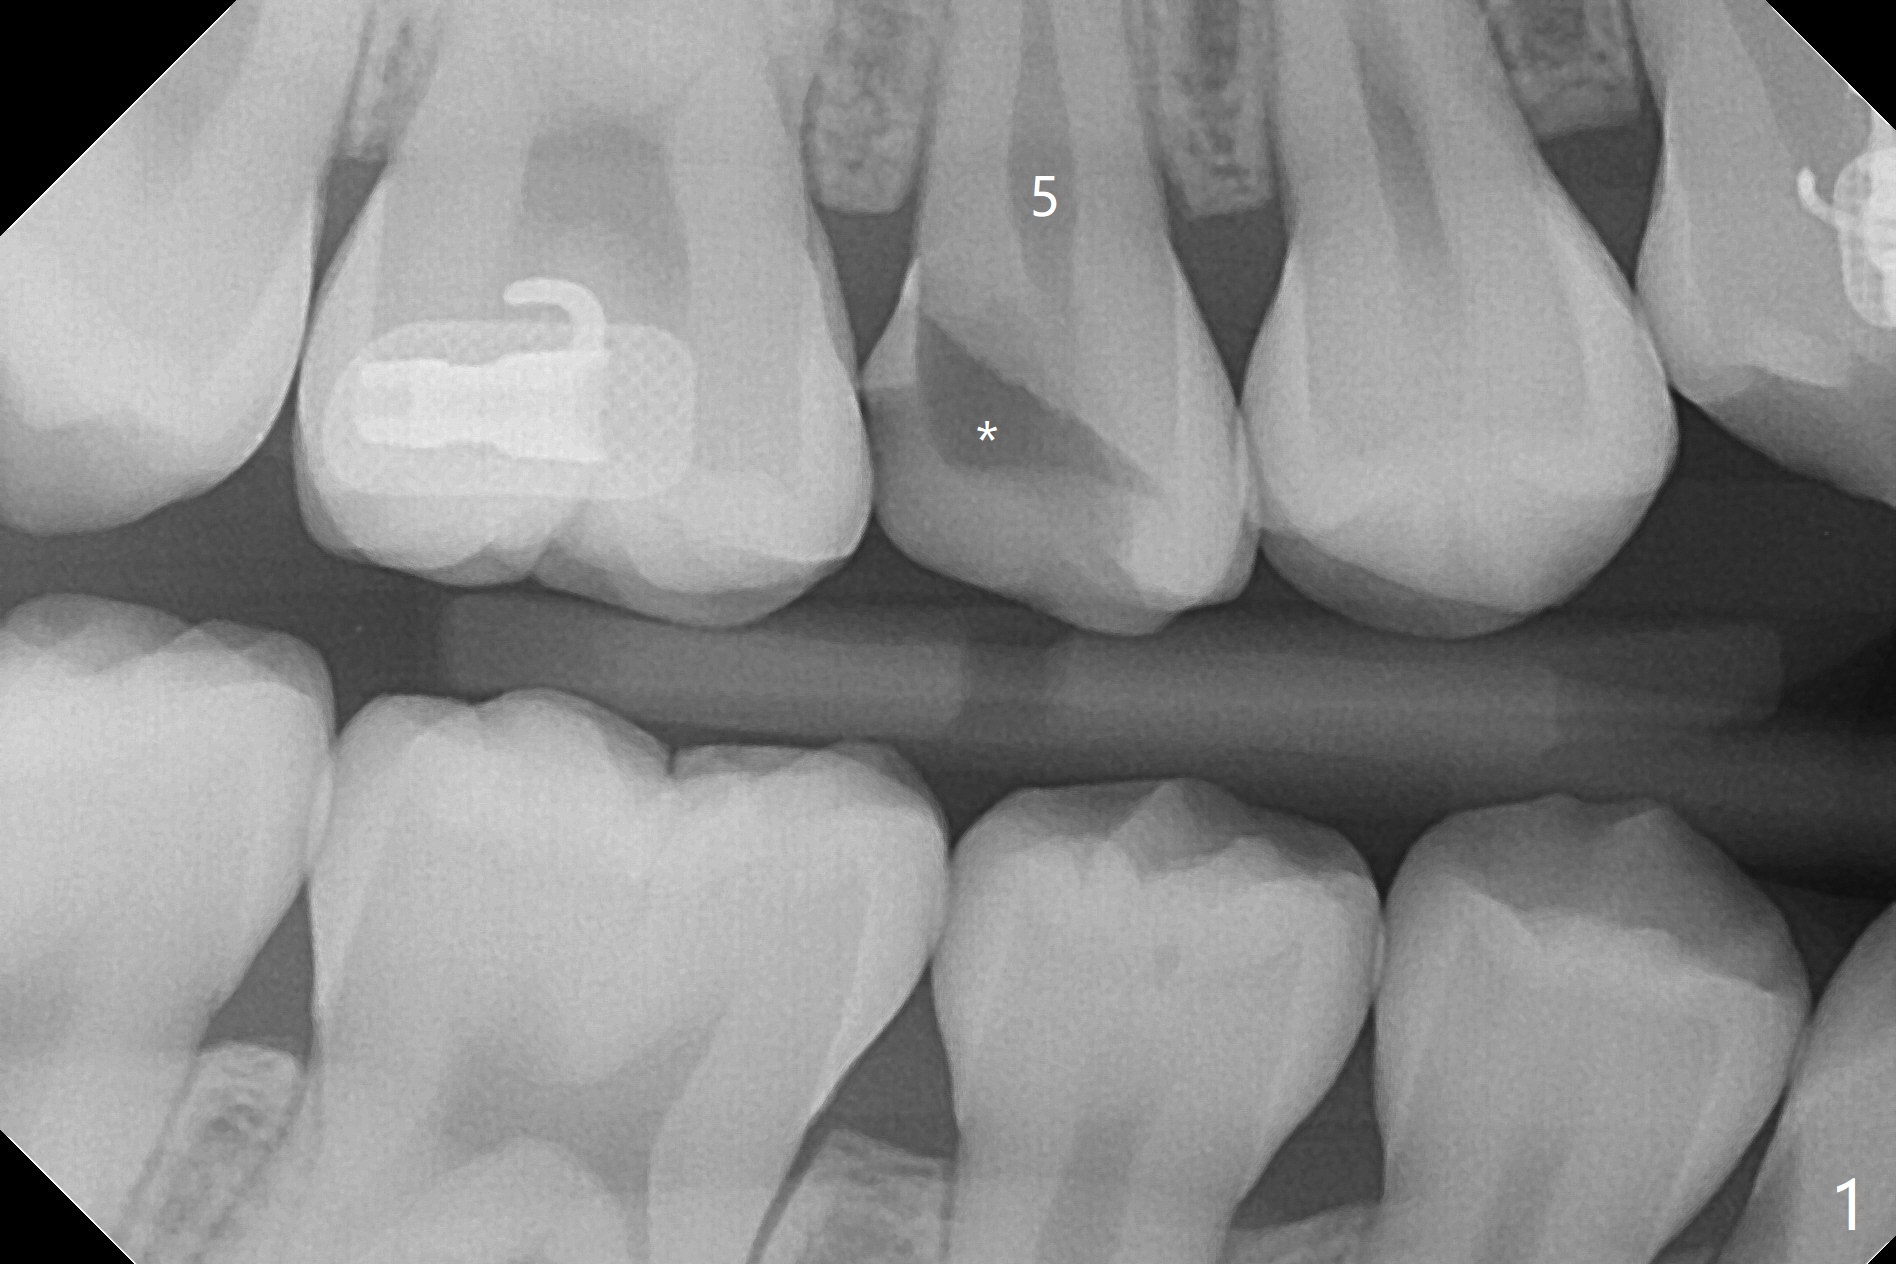

A 14-year-old woman with crowding returns to clinic for extraction of the 1st bicuspids. Orthodontic treatment has started partially. Because of severe caries at UR5 (Fig.1 *), BWs and PA are taken, which reveal DO incipient caries at UL, LL5 (Fig.2) and large PARL at UR5 (Fig.3 *). Upon receiving a revised treatment plan, four of 2nd bicuspids are extracted. The large PARL is confirmed intraop. Examination of the extracted teeth shows mesial caries at UL5, which is not detected by X-ray (Fig.4 <). By comparison, DL caries of UL5 is more severe (Fig.5). Check the neighboring teeth for caries when the patient returns for recall. The pulpal exposure of UR5 is large (Fig.6). So is the pulpal chamber (Fig.7). The large canal (Fig.7) in fact consists of 2 ones (Fig.11 red arrows) with a separation in between (*). The DL caries at LL5 is at the stage of decalcification (Fig.8), not visible in X-ray (Fig.12, as compared to Fig.7 >).